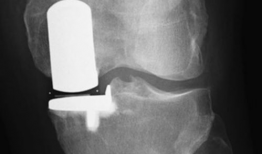

• 膝关节置换手术视频,从术前准备到术后康复

你有没有想过,当你的膝关节像老化的弹簧一样“嘎吱嘎吱”作响时,会有一种神奇的手术能把它换成一个全新的呢?没错,就是膝关节置换手术...